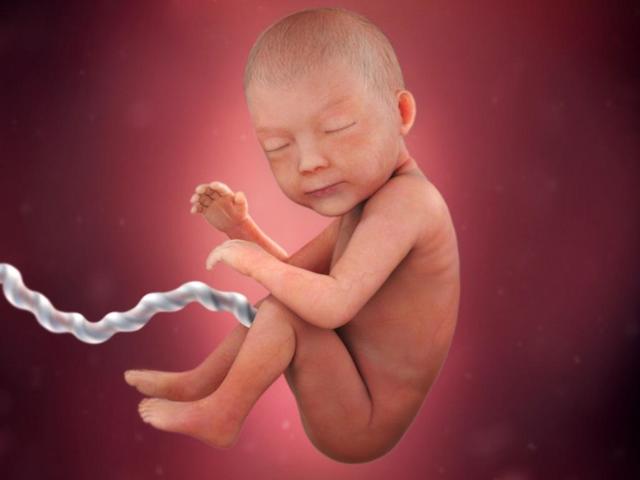

• Third Trimester (eighth month)

Third Trimester (eighth month)

Gains two to three pounds, shed lanugo, head moves into down position, can move and change positions, lungs finish developing. The mother may experience back aches, leg cramps, and fatigue.